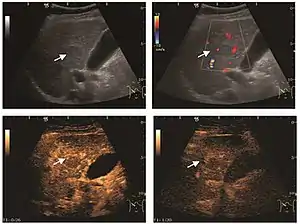

The ultrasound appearance is a well defined lesion, with very thin, almost unapparent walls, without circulatory signal at Doppler or CEUS investigation. The content is transonic suggesting fluid composition. The presence of membranes, abundant sediment or cysts inside is suggestive for parasitic, hydatid nature. Posterior from the lesion the acoustic enhancement phenomenon is seen, which strengthens the suspicion of fluid mass. They typically displace normal liver vessels but no vascular or biliary invasion occurs.

Hydatid liver cyst. Diagnostic criteria are the presence of membranes and sediment inside.

It is the most common liver tumor with a prevalence of 0.4 – 7.4%. It is generally asymptomatic but also can be associated with pain complaints or cytopenia and/or anemia when it is very bulky. It is unique or paucilocular. It can be associated with other types of benign liver tumors. Characteristic 2D ultrasound appearance is that of a very well defined lesion, with sizes of 2–3 cm or less, showing increased echogenity and, when located in contact with the diaphragm, a "mirror image" phenomenon can be seen. When palpating the liver with the transducer the hemangioma is compressible sending reverberations backwards. Doppler exploration reveals no circulatory signal due to very slow flow speed. CEUS investigation has real diagnosis value due to the typical behavior of progressive CA enhancement of the tumor from the periphery towards the center. The enhancement is slow, during several minutes, depending on the size of hemangioma and on the presence (or absence) of internal thrombosis. During late (sinusoidal) phase, if totally "filled" with CA, hemangioma appears isoechoic to the liver. Deviations from the above described behavior can occur in arterialized hemangiomas or those containing arterio-venous shunts. In these cases, differentiation from a malignant tumor is difficult and requires other imaging procedures, follow up and measurements of the tumor at short time intervals.[4]